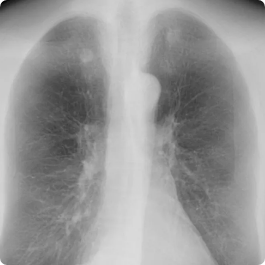

Lung cancer and coronary disease are worldwide leading killers and early detection is key to improving outcomes. CAC affects 20 million Americans annually, yet over half of incidental findings go unreported.12,13 Lung cancer is the leading cause of cancer death and nodule search is burdensome, and vessels can obscure findings, delaying diagnosis. Findings are time-consuming to compare over time, segment, and quantify. In addition, exploding imaging volume and radiologist shortages and burnout are at a breaking point.